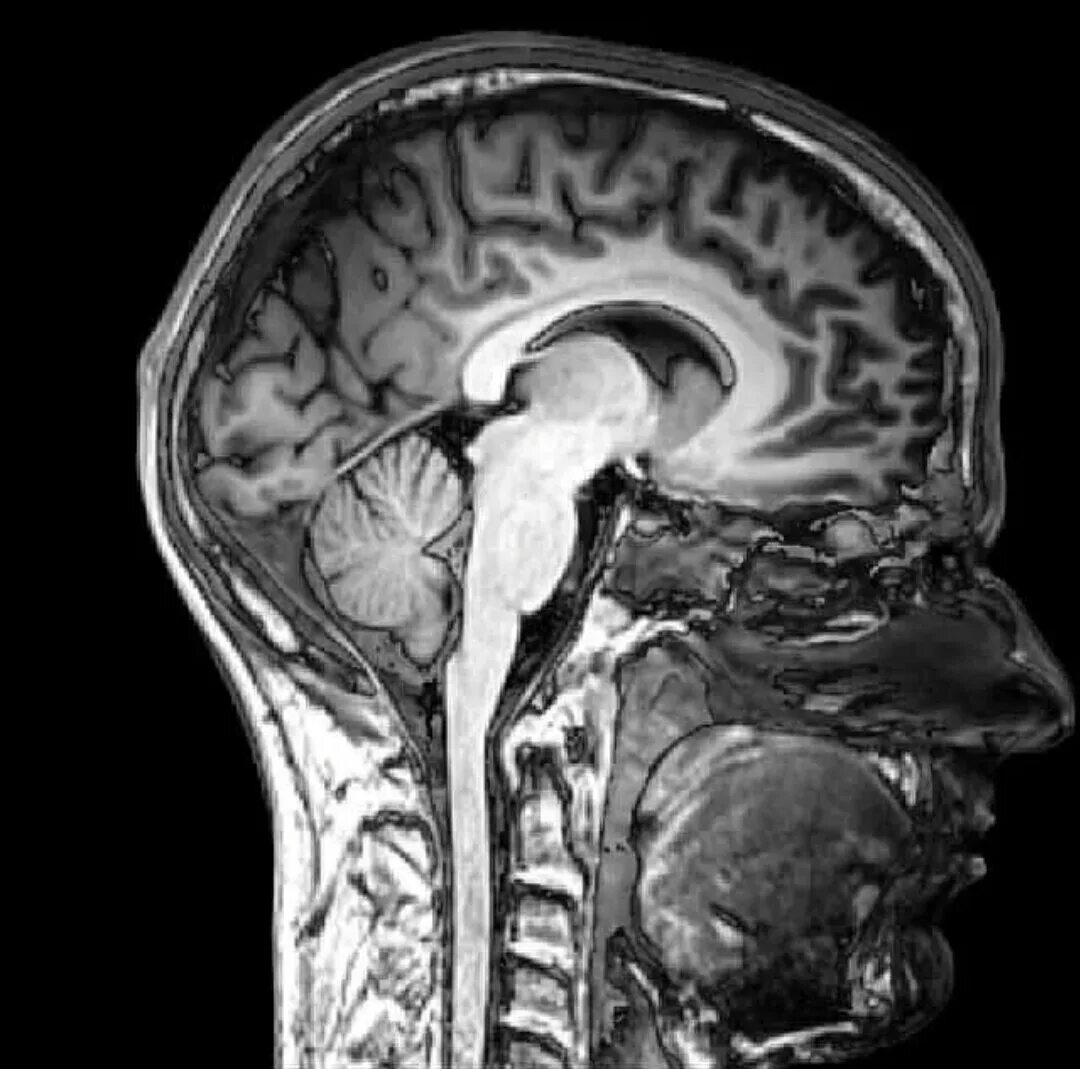

Томограмма головы